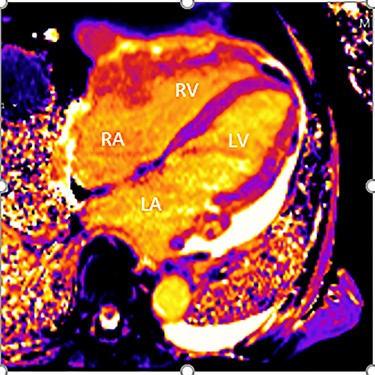

Intraoperatively, he developed new t-wave inversion on lead II of the 3-lead electrocardiogram (ECG). This resolved post-operatively, and he denied chest pain. He was kept in overnight for observation. The next morning, during the round, he reported central crushing chest pain the previous day that he had not disclosed. His ECG was repeated and demonstrated the t-wave inversion in lead II—indicating dynamic ECG changes. A troponin I level measured 27. As such, management for a non-ST elevation myocardial infarction was initiated and a cardiology consult organized, who advised continued acute coronary syndrome (ACS) treatment and an echocardiogram. This demonstrated a ‘pericardial mass (subcostal 3 cm × 2.5 cm) encroaching and extending outwards on both sides of the right atrioventricular groove’. ACS protocol was stopped and a cardiac magnetic resonance imaging (MRI) was organized (Figs 2 and 3).

Cardiac MRI (transverse plane) demonstrating an enhancing lesion surrounding the chambers of the heart.

This demonstrated a bulky mediastinal tissue (measuring 50% of the heart) that encased all the aorta and pulmonary artery as well as the coronary artery. It has malignant behaviour with multiple foci that breached fascial planes. It restricted the long axis of the heart but was not causing haemodynamic occlusion. It was non-resectable.